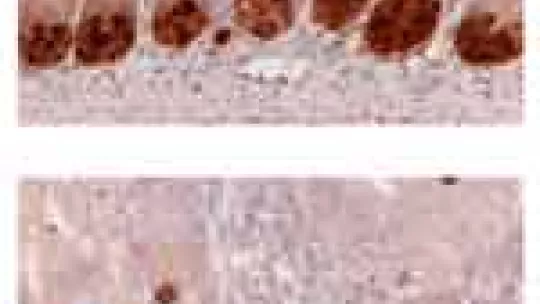

The so-called EphB receptors, present in the cells at the bottom of the crypts, bind to Ephrin ligands located mainly in differentiated cells in the upper part of the intestinal epithelium. The ligand-receptor binding occurs at the frontier between the two cell populations and controls cell positioning in the tissue. However, until now, the way in which these ligand-receptor bindings instruct cells to position themselves in one place or another was unknown.

The results of this study demonstrate that EphB-ephrin bindings activate the metaloprotease ADAM10, which destroys the binding between distinct cell types, such as between cells from the bottom and surface of crypts. It is the destruction of these binding between cells from distinct compartments that prevents cell mixing, thus impeding once cell type from entering the wrong territory. In the words of Guiomar Solanas, first author of the article, “we have found the molecular mechanisms by which EphB receptors and their ligands tell each cell where it has to be throughout its life: from its generation from stem cells in the crypt bottom until its differentiation”.